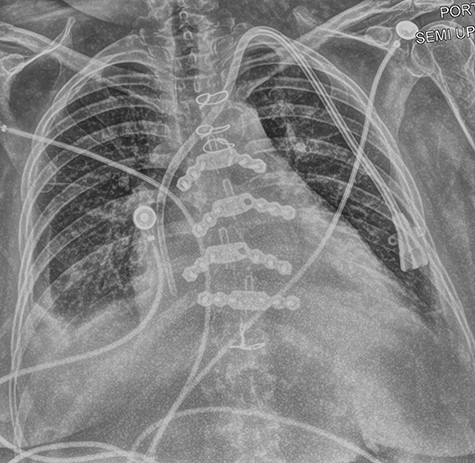

A left internal jugular tunneled dialysis catheter was placed under direct visualization with the tip below the cavoatrial junction for dialysis in the postoperative period. Mediastinal drains were placed, and the sternum was closed with two titanium plates, screws and wires. Chest x-ray can bee seen in Fig. 2.

Patient was discharged on post-op day 7, however had a complicated course post discharge with readmissions for central venous thrombosis, pulmonary emboli, sternal dehiscence with osteomyelitis secondary to coagulase negative staphylococcus, bacteremia with the same organism, complicated hardware extraction with sternal reconstruction and flaps. Overview of complications can be seen in Fig. 3. At time of writing, the patient had been seen at outpatient follow-up and was doing well, with removal of her tunneled dialysis catheter and a working right upper arm arteriovenous fistula.